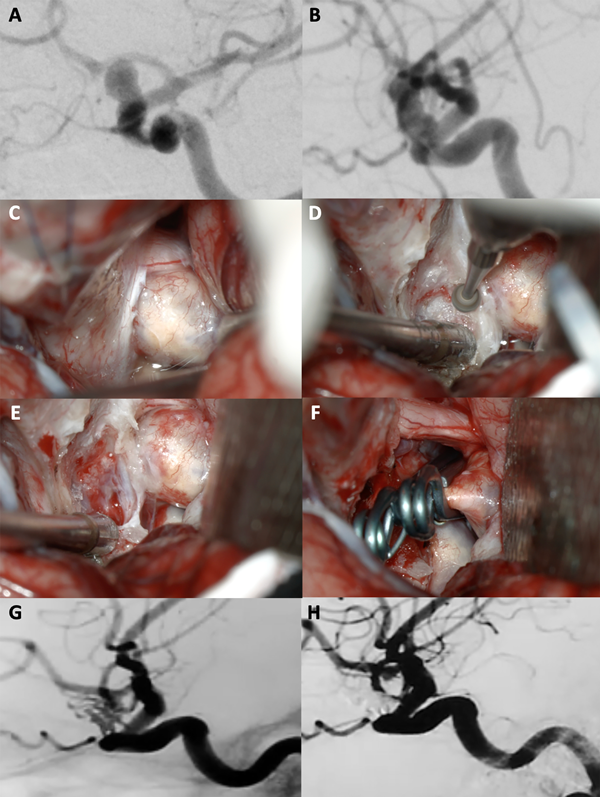

Figura 4. A-B: Se aprecia una arteriografía cerebral con reconstrucción tridimensional que evidencia un aneurisma carótido oftálmico izquierdo, nótese como la arteria oftálmica sale del domo del aneurisma. C-F: Fotografías intraoperatorias. Observamos la cisterna óptico-carotidea donde es visible el saco aneurismático ejerciendo gran efecto de masa sobre el nervio óptico. Posteriormente se realizó una clinoidectomía anterior parcial logrando una adecuada exposición del cuello del aneurisma. Se muestra la exclusión del aneurisma con un clip angulado. G-H: Imágenes de arteriografía cerebral post operatoria que evidencia la exclusión completa del aneurisma con preservación de la arteria oftálmica.

Figura 5. A-B: Se aprecia una arteriografía cerebral que evidencia un aneurisma carótido oftálmico izquierdo gigante. C-F: Fotografías intraoperatorias. Observamos la cisterna óptico-carotidea donde es visible el saco aneurismático ejerciendo gran efecto de masa sobre el nervio óptico, no es visible la arteria carótida. Posteriormente se realizó una clinoidectomía anterior total y sección del anillo dural distal logrando una adecuada exposición del cuello del aneurisma. Se muestra la exclusión del aneurisma con dos clips rectos. G-H: Imágenes arteriografía cerebral post operatoria que evidencia la exclusión completa del aneurisma con preservación de la arteria oftálmica.